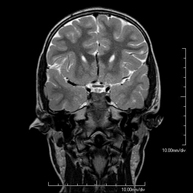

- Brain MRI (cranial)

This non-invasive diagnostic procedure uses an electromagnetic field and radio waves (from a transmitter and receiver) to acquire high-definition anatomical images of the brain. It is a radiation-free procedure. Indicated for: vascular problems, memory loss, epilepsy, headache, malformations, suspected tumour, meningitis.